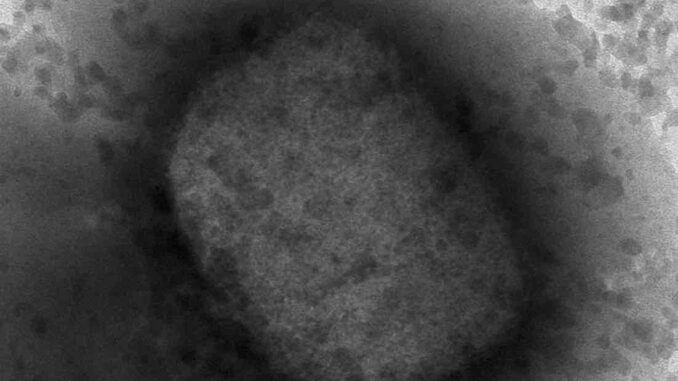

El director general de la Organización Mundial de la Salud (OMS) aconsejó hoy, 27 de julio de 2022, a los hombres en riesgo de contraer viruela del mono que limiten “por el momento” el número de sus parejas sexuales después que la agencia de la ONU declaró la emergencia global de la enfermedad.

Tedros Adhanom Ghebreyesus dijo que el 98% de los casos detectados desde que comenzaron los brotes en mayo han sido en hombres gay, bisexuales y otros que tienen relaciones sexuales con hombres. Pidió a los que están en riesgo que tomen medidas para protegerse.

Funcionarios de la OMS destacaron que la viruela del mono puede trasmitirse mediante el contacto estrecho con un paciente, su ropa contaminada o su ropa de cama. La agencia ha advertido que los niños y las mujeres embarazadas son una población vulnerable a la enfermedad.

Hasta la fecha se han reportado más de 19.000 casos en 75 países; solo se han registrado muertes en África.